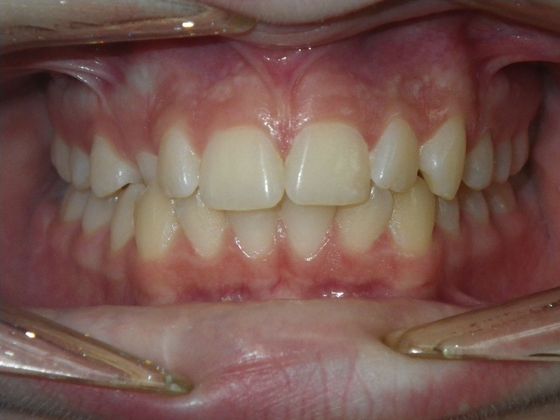

This patient had an upper right permanent cuspid that was impacted and would need uncovering by oral surgeon who would place bracket with chain to help enable us to tease the permanent cuspid into its proper position. She also had a permanent 2nd Molar that was impacted due to improper development of 3rd molars and the oral surgeon could remove them at the same time as uncovering of the permanent cuspid. After uncovering and removal of lower 3rd molars, we would begin comprehensive straight wire orthodontic treatment.